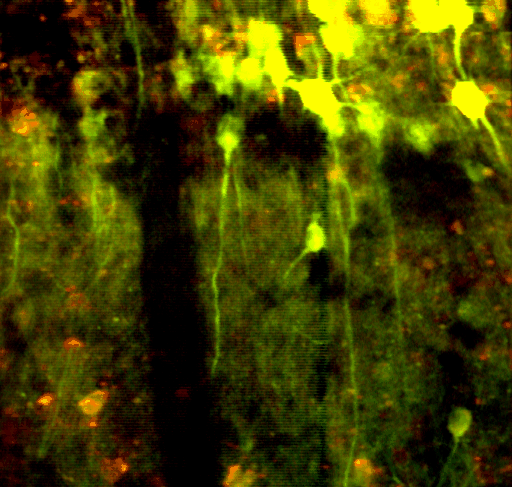

This is the second layer of the hippocampus, a structure within the brain responsible for spatial-temporal coding. Here, you're able to look at the specific braincells, called neurons, responsible for the incredibly complex behavior each of us exhibit daily.

This image was taken with a microscope that I designed and built at the California Nano-Systems Institute in Los Angeles, California.